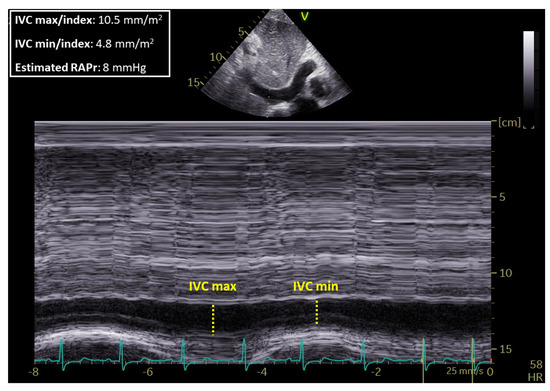

| IVCmax_Index (mm/m2) | 10.3 ± 2.84 | 7.80 ± 2.25 | 0.006 |

| IVCmin_Index (mm/m2) | 4.46 ± 3.81 | 2.38 ± 2.61 | 0.04 |

| CI_ivc (%) | 58.18 ± 33.87 | 70.41 ± 29.46 | 0.27 |

| RAPr (mmHg) | 7.39 ± 2.96 | 5.57 ± 1.62 | 0.01 |